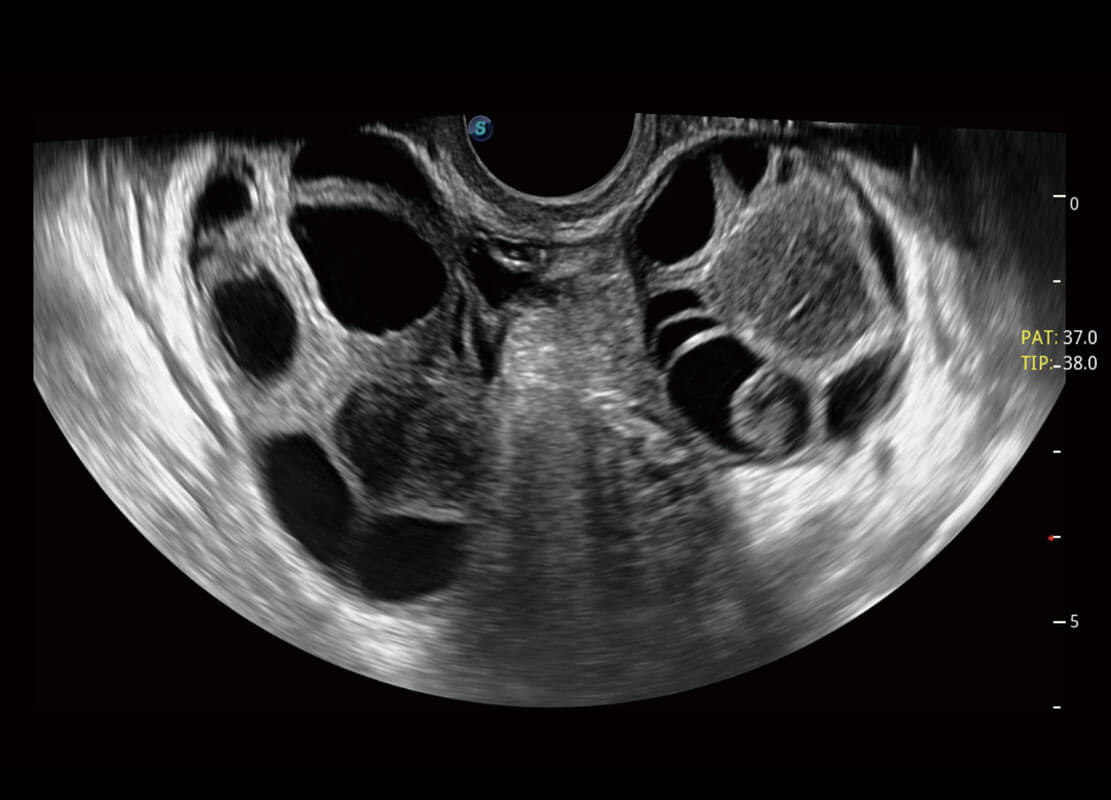

腔内妇科-卵巢

腔内三维-宫内节育器